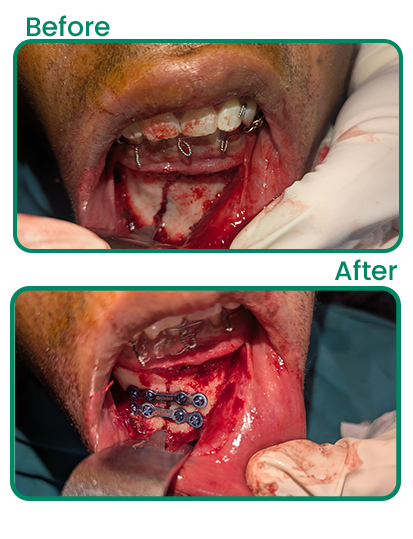

Zygomatic Implants

Specialized implant solution for patients with low bone density, providing strong support without the need for bone grafting.

Facial Trauma & Jaw Injuries

Facial Trauma & Jaw Injuries